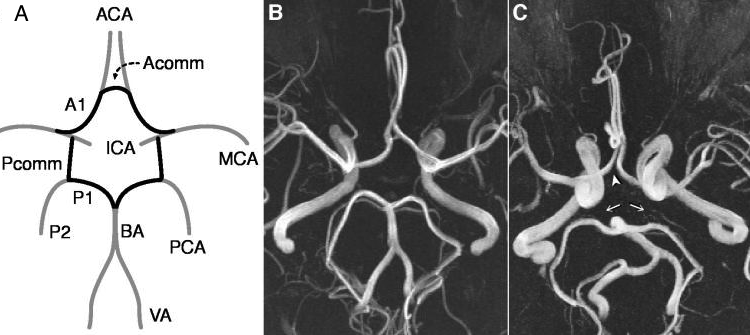

ウィリス動脈輪についての概要 ウィリス動脈輪は、脳底部に位置し、脳の血液供給を安定させる重要な構造です。主要な動脈は以下の通りです。 前交通動脈 は、左右の前大脳動脈をつなぎ、前部の血液循環を支えます。 中大脳動脈は、内頸動脈から分岐し、側頭葉や前頭葉に。

大脳動脈輪 ウィリス動脈輪前方循環系の前大脳動脈・中大脳動脈と、後方循環系の後大脳動脈 が脳底で輪状に連絡しあったものです。トルコ鞍 視交叉と下垂体 を囲むように輪を作ります。 構成 ・前大脳動脈 ACA・中大脳動脈 MCA・後大脳 動脈 PCA。

脳底を走行する動脈 内頸動脈系の前大脳動脈・中大脳動脈と、椎骨動脈系の後大脳動脈が、脳底で輪状に連絡し合い、大脳動脈輪 ウィリス動脈輪 を形成します。 ウィリス動脈輪は、トルコ鞍 視神経交叉と下垂体 を囲むように輪を作ります。 構成: 前大脳動脈、中大脳。

ごろ~にゃ@画像診断cafe on X: " 🧠Willis動脈輪とは?🧠☑️内頸動脈 C1 ☑️前大脳動脈 A1 ☑️前交通動脈 A-com☑️後交通動脈 P-com ☑️後大脳動脈 P1 で構成され、これらの動脈が吻合してできる輪状または六角形の輪のことです。脳のMRA画像を読影する上で。